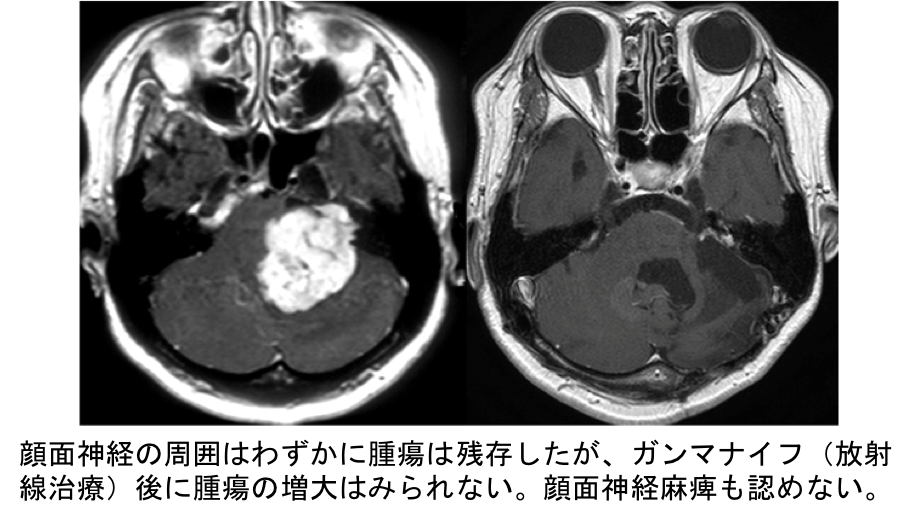

聴神経腫瘍は頭蓋内の末梢神経にできる神経鞘腫のうち、一番頻度が高い良性の腫瘍です。通常は、耳鳴りや聴力低下などの聴覚症状で発症しますが、ふらつきやめまい、顔面や舌のしびれなどで発症することもあります。また、突発性難聴と診断されて腫瘍の発見が遅くなることもあります。

治療方針としては、経過観察、手術による摘出、定位放射線治療があり、患者さんの年齢や全身状態、腫瘍の大きさ、聴力の状況など、さらには患者さんの意向も加味して、最善の治療方針を決定します。手術による全摘出が根治的ですが、聴神経腫瘍手術による特有の合併症があります。聴神経腫瘍は、脳幹と小脳との間に存在しており、周囲にはさまざまな神経が走行しています。手術によって聴力の低下や、顔面神経麻痺、めまいやふらつき、嚥下障害や嗄声、複視などがおこることがあります。また、小脳が腫れたり出血した場合には意識障害や場合によっては生命にかかわる深刻な合併症へと発展することもありえます。当科では手術合併症を回避し安全な手術を目指します。したがって、危険と判断した場合には無理な摘出は行わずにあえて腫瘍を残存させて、定位放射線治療(ガンマナイフ)をおこなうこともあります。